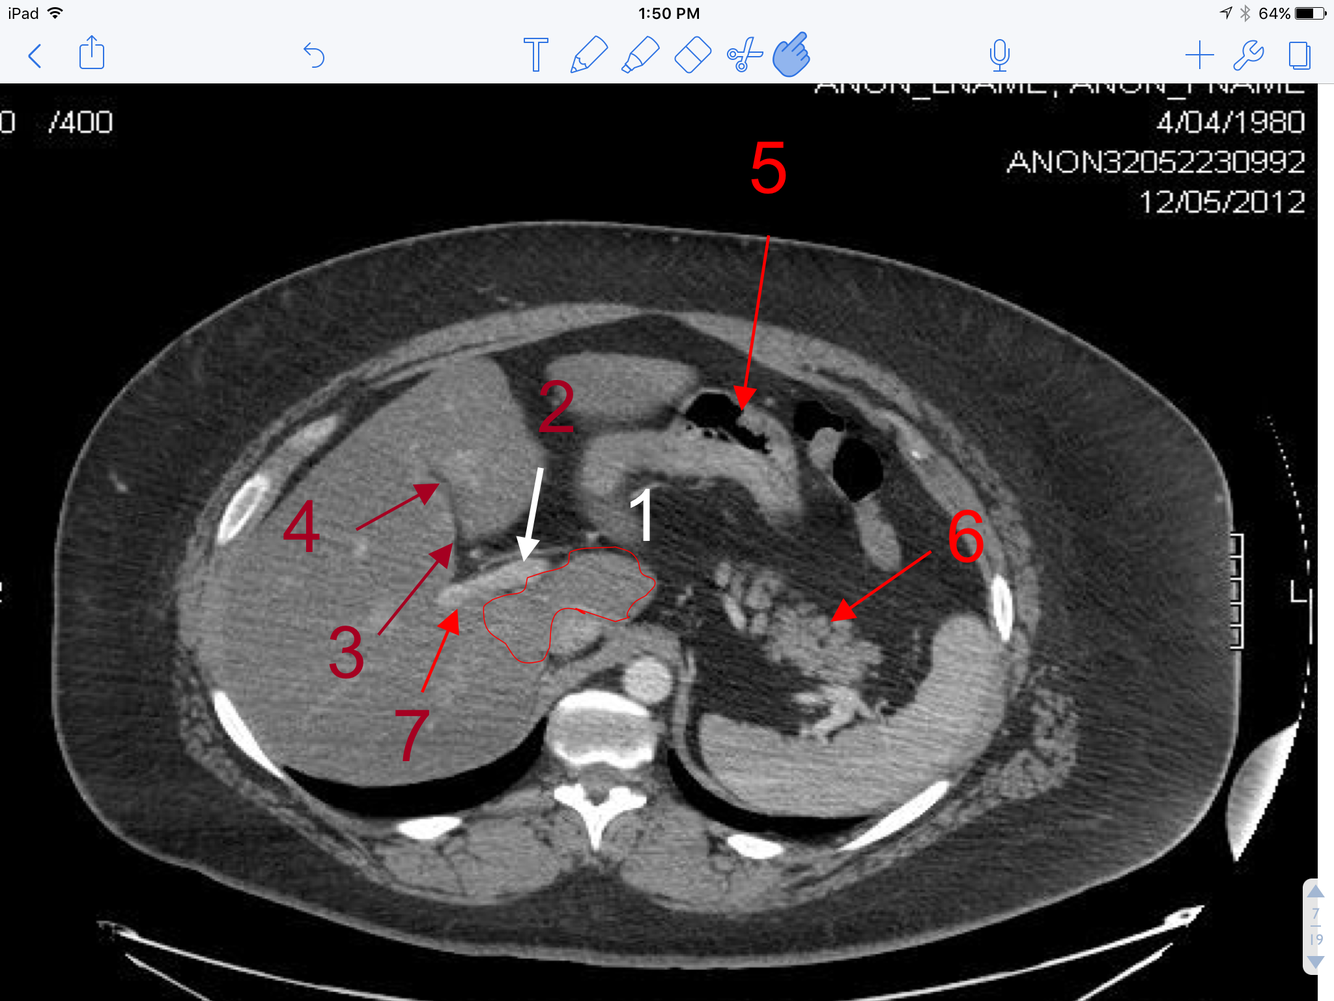

5

Q

A

1. Caudate lobe of the liver (outlined)

2. Lt branch of the portal vein

3. Cystic duct of the gallbladder

4. Neck of the gallbladder

5. Gas in the body of the stomach

6. Tail of Pancreas

7. Rt branch of the portal vein